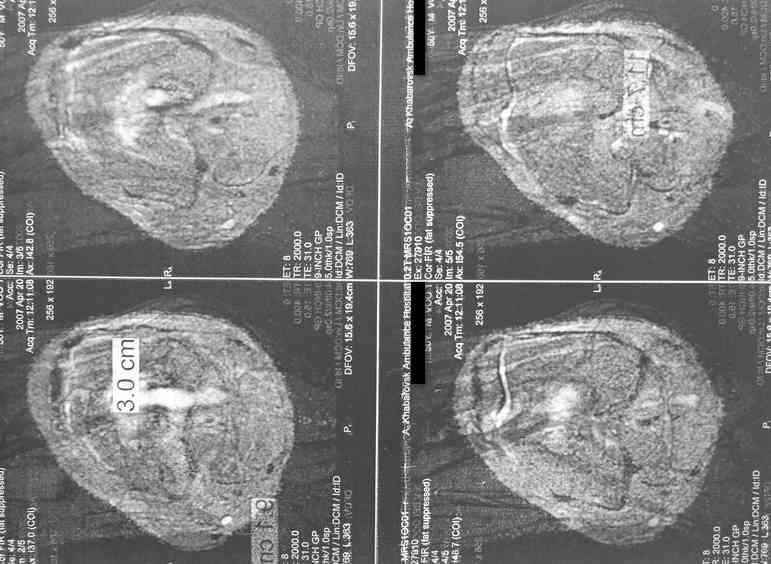

Больной 53 лет, страдает остеомиелитом с 1975г.,после закрытого перелома с/3 бедра и интрамедулярного остеосинтеза. Выполнено более 30 операций без особого эффекта. Какой комплекс операций может помочь больному? Больной, 1954 г.р.Клинический диагноз: хронический травматический тотальный остеомиелит левой бедренной кости, секвестрально - свищевая форма, часторецидивирующее течение. Ложный сустав шейки левой бедренной кости. Укорочение левого бедра 10 см. Контрактура коленного сустава. Жалобы: боли в области левого бедра, коленного сустава, нарушение функции левой ноги, наличие свища с гнойным отделяемым в левой подколенной области, свища в области в\з бедра. Анамнез: в 1975 г. получил закрытый перелом с\з левой бедренной кости. Оперирован в районной больнице - выполнена открытая репозиция, интрамедуллярный остеосинтез. Осложнение - нагноение раны с исходом в остеомиелит бедренной кости. В последующий годы - трижды патологический перелом бедра. Оперирован за эти годы около 30 раз по поводу обострения остеомиелита. За последние 5 лет обострения ежегодно по 2- 3 раза в год. Динамика отрицательная. Рентгенологически - тотальное поражение бедренной кости. Объективно: передвигается при помощи костылей с дозированной нагрузкой на левую ногу. При нагрузке на левую ногу - стопа в положении эквинуса, опора на передний отдел стопы. Выражена атрофия мышц левого бедра, голени. На всем протяжении бедра - множественные рубцы после оперативных вмешательств. В в\з бедра по наружной поверхности - грубый втянутый рубец с вялогранулирующей раной на дне его. Отделяемого нет. В области подколенной ямки - свищ с гнойным отделяемым серо - зелоноватого цвета без запаха. Укорочение бедра 10 см. Движения в тазобедренном суставе активно 180 - 160 град., пассивно 180 - 90 град. В коленном уставе 178 - 110 град. Чувствительных расстройств конечности нет.Лабораторные данные: Общ. ан. крови: 20.04.07. Нв-135 г\л, Er 4.22 млн., Le-9.7 тыс, Эоз. 4%, Пал.-5 %, Сегм.-60 %, Лимф. - 25 %, Моноц.-6 %, СОЭ 51мм\час.Биохимический ан. крови от 20.04.07г. Белок -77 г/л, сахар крови 5.38 ммоль/л., билирубин 10.2 мкмоль/л. Тимоловая проба 2.5 ед.пом. Ан.мочи от 20.04.07. : отн. плотность1026, белок - отр, сахар -отр, ЭКГ от 22.02.07 : отклонение ЭОС влево.. Неполная блокада правой ножки пучка Гиса. Флюорография от 28.12.2006 года № 038 - без патологии. R - графия : грубая деформация и склерозирование бедренной кости от проксимального до дистального метафиза , множество очагов просветления в области дистального метаэпифиза, н\з бедра. МРТ коленного сустава, н\з бедра от 21.04.2007г. - картина хронического остемиелита левой бедренной кости. Имеется полость деструкции в дистальном метадиафизе протяженностью до 12 см. Полость имеет неоднородное содержимое за счет гноя, грануляций, секвестров, сообщается со свищевым ходом, идущим в подколенную ямку.